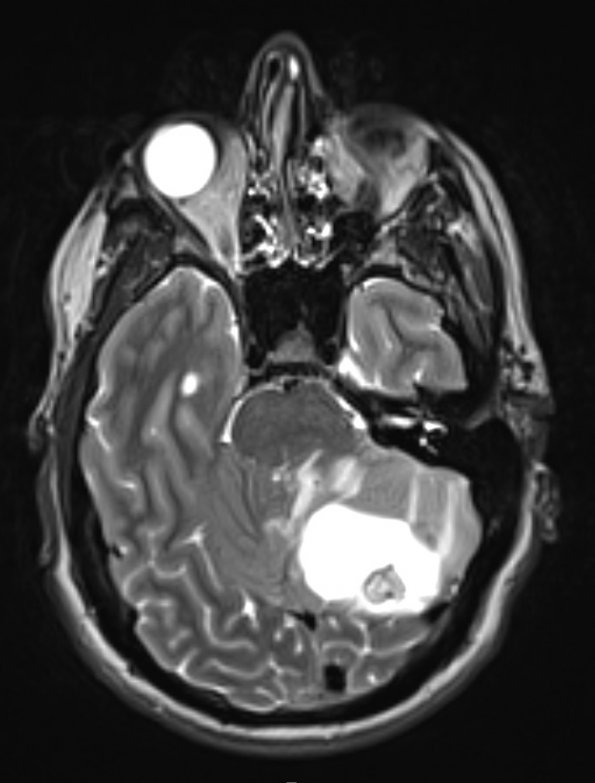

A T2-weighted scan with contrast illustrates a hyperintense cyst and a less intense mural nodule.